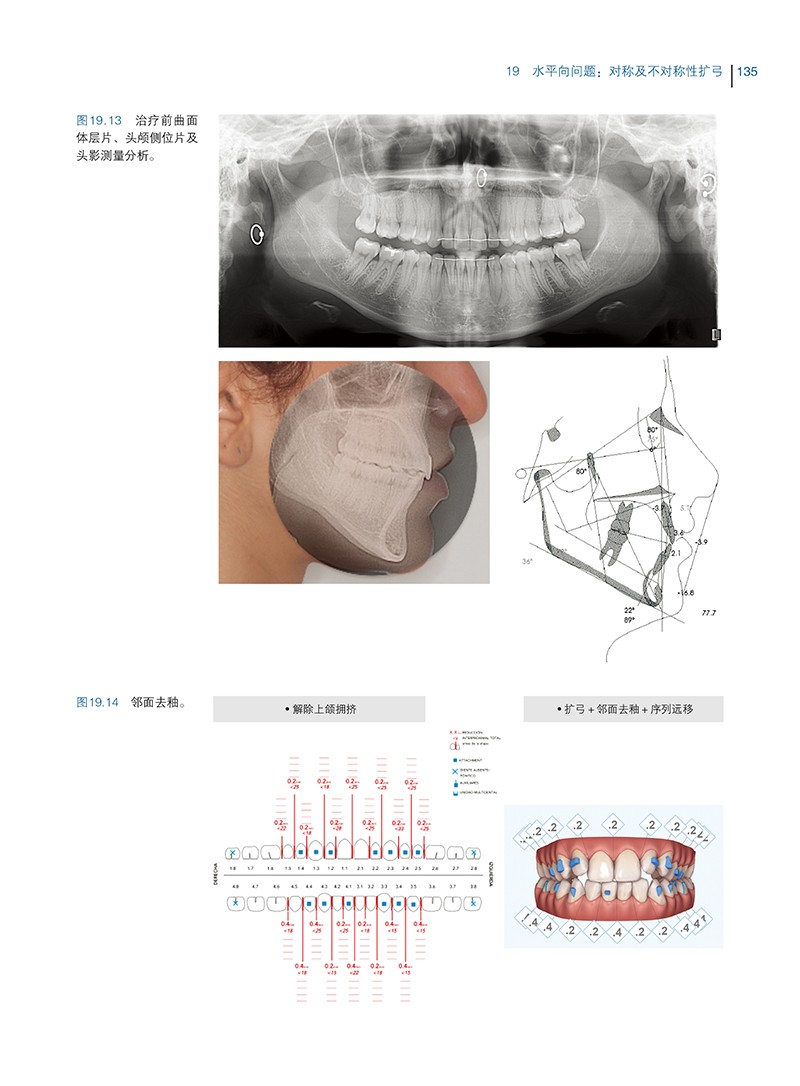

19 水平向问题:对称及不对称性扩弓 130

19.1 扩弓病例应注意的问题 132

19.2 对称性扩弓 133

19.2.1 牙弓狭窄所致的前牙开 133